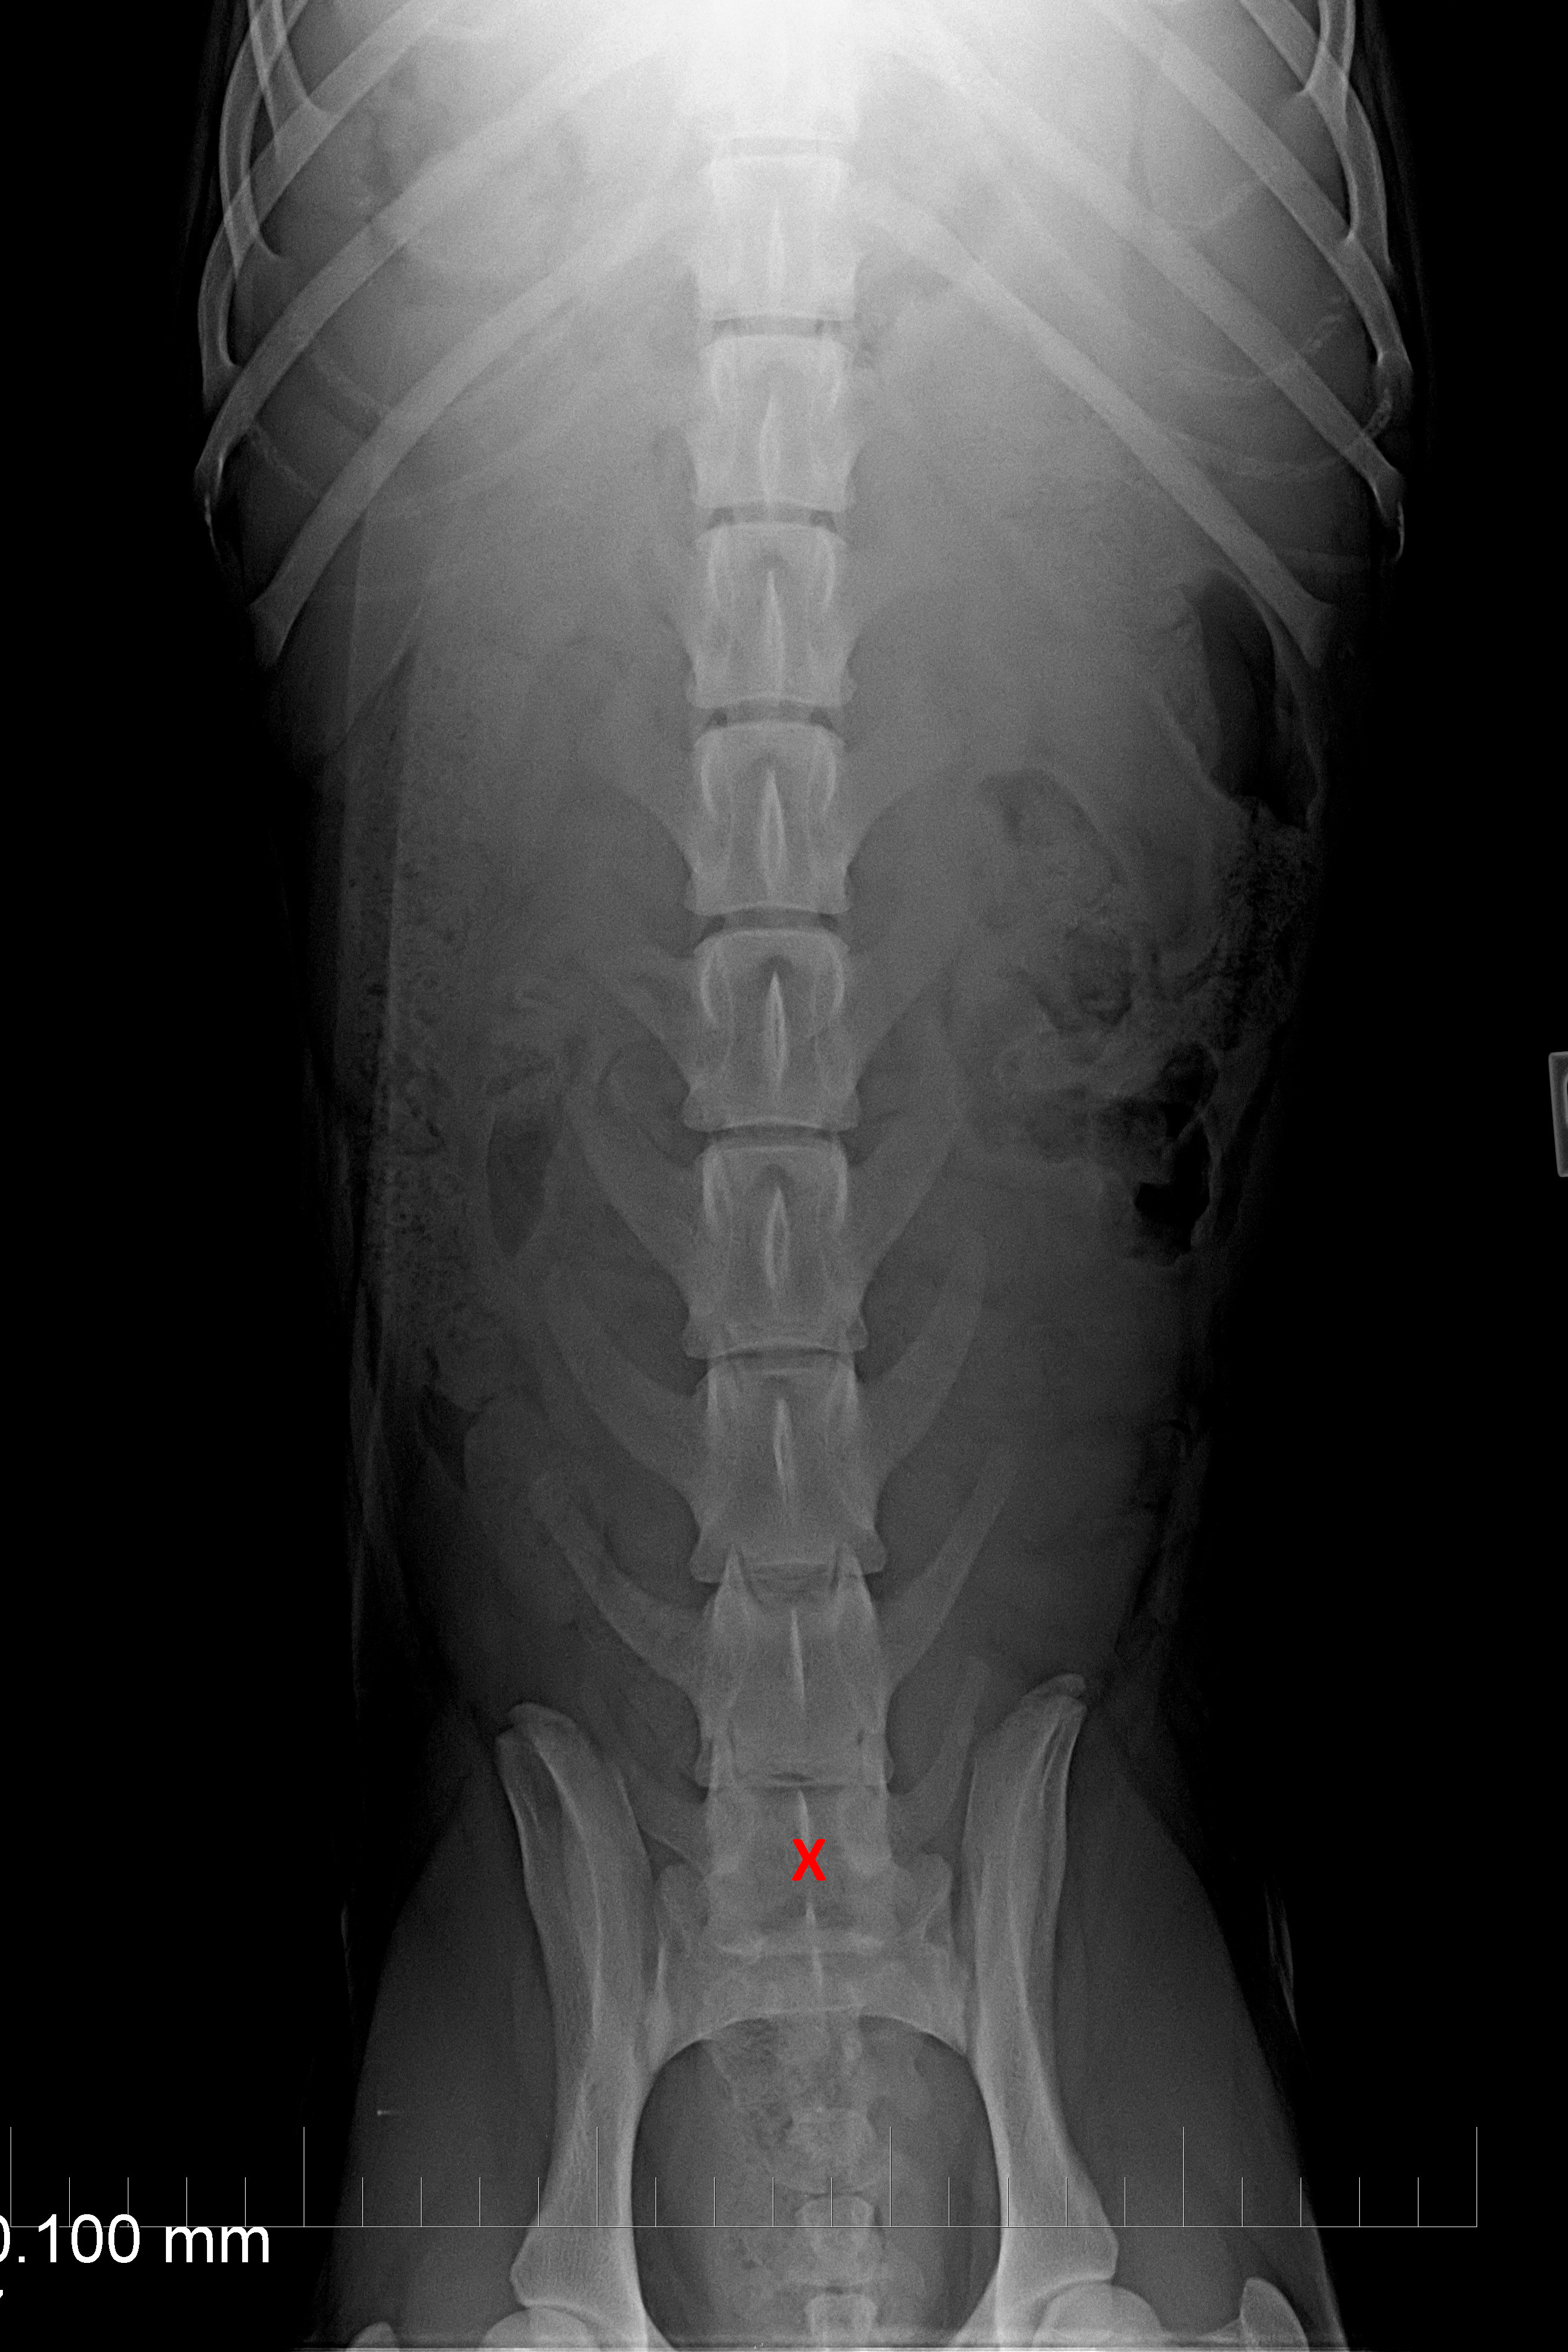

(3) 7 měsíců VD 1

(3) typ 3 po korekci polohy pánve

(4) 7 měsíců VD 2

(4) typ 3 po korekci polohy pánve 2

(5) typ 3 páteř VD